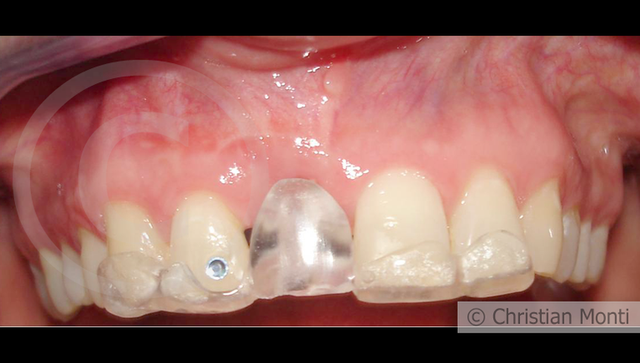

EDENTULIA SINGOLA

Impianto in sostituzione di un incisivo superiore